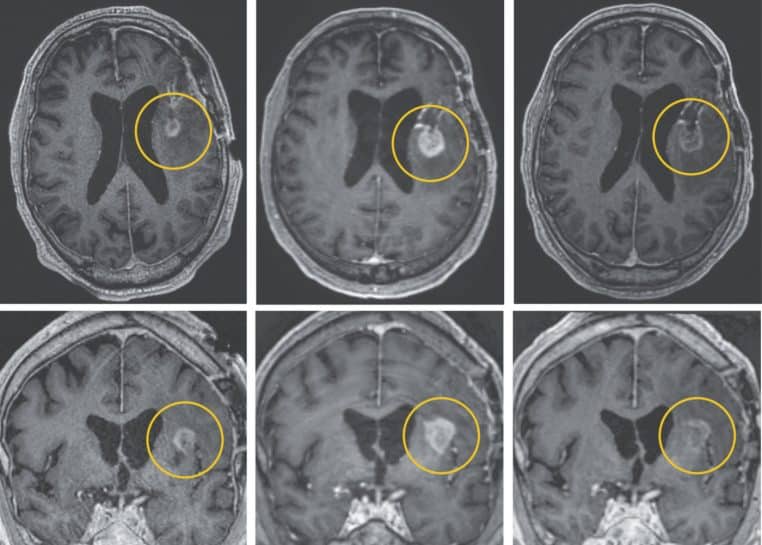

Les trois patients sont touchés par un glioblastome. Cela se traduit par la croissance de cellules cancéreuses dans le cerveau et la moelle épinière, qui détruisent les tissus sains.

« Quelques jours seulement après un seul traitement, les patients ont constaté une réduction spectaculaire de leurs tumeurs. Un patient ayant atteint une régression tumorale presque complète » indique le Mass General Brigham. Ce patient n’est autre que la femme âgée de 57 ans.

Une régression presque complète au bout de 5 jours !

Les chercheurs sont stupéfaits par les résultats. La patiente de 57 ans a vu son cancer disparaître presque totalement.

Après avoir effectué une IRM 5 jours après la première perfusion, elle a découvert que la tumeur avait presque disparu. « La thérapie CAR-T a révolutionné notre façon de penser le traitement des personnes atteintes de cancer » estime Bryan Choi, neurochirurgien.

Selon les chercheurs, les résultats ont été un peu plus longs. Au bout du 69ème jour, l’homme de 72 ans a vu une régression de 60,7% de sa tumeur. Le message est donc le suivant : les recherches pour la lutte contre le cancer sont positives.